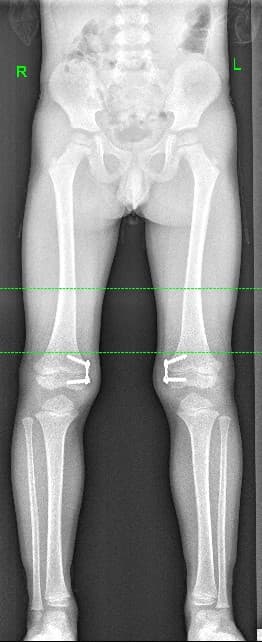

Пример применения гемиэпифизиодеза №2:

Идиопатичпеская вальгусная деформация бедер

Через 8 месяцев­­­